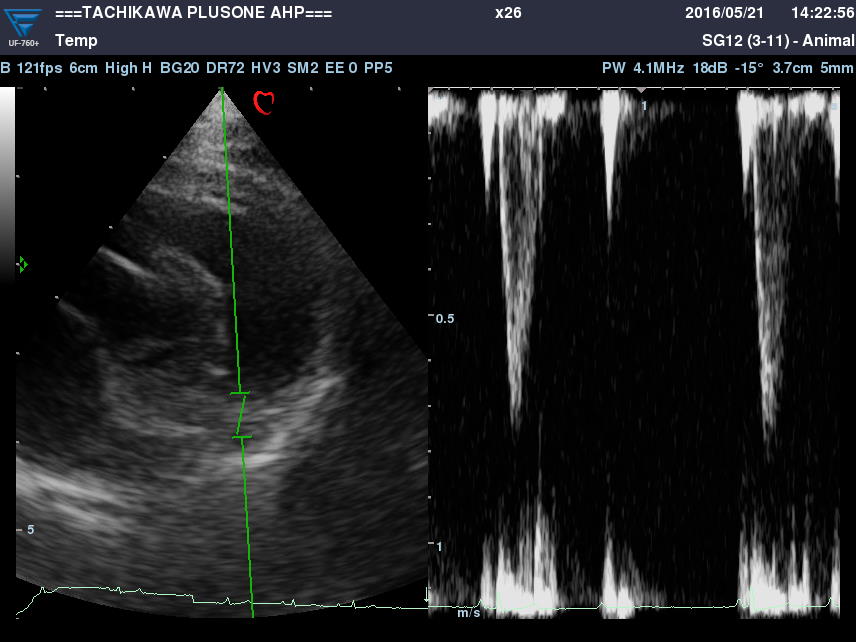

・心エコー検査(心超音波検査)

心臓の状態を把握し治療方針を決定するのに欠かせない検査です。

心臓の細部構造や動きの観察をします。

また、血液の流れる向きやスピードの計測が出来ます。